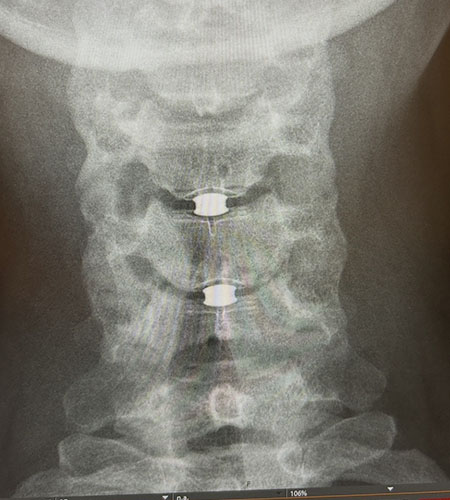

The synthetic discs consist of a ceramic core sandwiched between two plates of medical-grade plastic coated with titanium. Their dynamic cores allow for flexible movement of the spine. The device has been approved for replacement of up to two adjacent discs.

To install the replacement discs, Khan made a small incision in front of Polach's neck and used a microscope and other precision instruments to remove the damaged discs. Under x-ray guidance, he sized the prostheses to relieve nerve pressure. He created small slots in her vertebrae and slid the new discs between them, ensuring their fit through imaging.